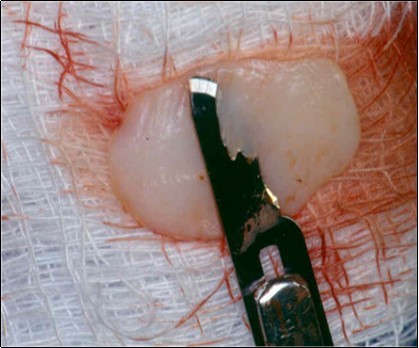

A second surgical site is created on the palate. The length of this is determined by the combines width of the teeth to be covered. The incisions are made in an anterior posterior direction. They are carried to the depth of the palatal mucosa, where they converge just short of the bone. A wedge of tissue is removed as free gingival graft, and its band of epithelium is excised by using Er:YAG laser and acute dissection with scalpel and blade 15C (Figure 4, Figure 4A). The graft is placed in the previously recipient site so that it completely covers the formerly exposed root area (Figure 5). It is then firmly sutured in place with 5-0 gut. The partial thickness, flap is positioned coronally in a manner to cover as much of the graft as possible and sutured in this position to promote maximum adaptation to ensure better healing with less chance of wound dehiscence (Figure 6). The donor site and recipient site is covered with surgical dressing and the patient is instructed in normal postsurgical management. The patient is seen on the 7th postoperative day to remove the surgical dressing and sutures. No additional dressing is necessary, and normal plaque control techniques are resumed (Figure 7)

Figure 4.Donor site area in the palate

Figure 4a.Elimination of the epithelium from free gingival graft by acute dissection